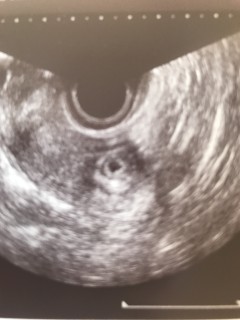

長い間不妊治療をしてきてようやく授かった命。 実は2ヶ月前に体外授精後、妊娠8週目で完全流産してしまい、辛かったけどここまで諦めないで頑張ってきて良かった。 つい先日、鮮血と下腹部痛に見舞われたけど止血剤と痙攣を止める薬を処方してもらい、なんとか無事。 赤ちゃん、このまま無事に元気に産まれてきてね。 4.2㎜でした。